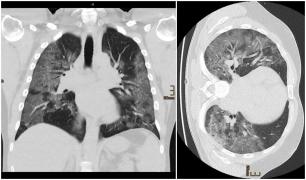

Cum arată radiografia la plămâni a unui medic infectat cu Covid-19

Cum arată radiografia la plămâni a unui medic infectat cu Covid-19Când a fost diagnosticat cu COVID-19, medicul Andre Bergmann a mers la spitalul Bethanien, din Moers, lângă locuința sa din...